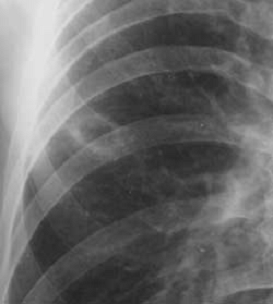

Одной из причин ошибочной диагностики периферического рака является неправильная трактовка рентгенологической картины. В сознании врачей периферический рак часто ассоциируется с округлым "шаровидным" образованием. Между тем периферический рак на разных этапах развития имеет разную макроморфологическую и и рентгенологическую картину.

Общепринятое мнение о шаровидной форме периферического рака справедливо только по отношению к относительно большим узлам, диаметр которых превышает 3-4 см. Большинство более мелких опухолей не имеет шаровидной формы и приобретает таковую только по мере роста новообразования. Сравнительно маленькие опухоли имеют вид очага уплотнения неправильной, амебовидной или звездчатой формы, неоднородной структуры с нечеткими, неровными контурами.

Иногда опухоль имеет несколько центров роста и выглядит в виде конгломерата сливающихся очагов уплотнения. Большое значение в диагностике периферического рака имеет симптом лучистости в виде веерообразно расходящихся отростков по периферии опухоли, так называемая Corona maligna (Приложение А рисунок 1). Этот симптом наблюдается примерно в 2/3 случаев периферического рака. Считается, что лучистость легочного рисунка вокруг опухоли, так же как и втяжение прилежащей утолщенной плевры, является выражением не только ракового лимфангита, но и сморщивания опухоли. Одновременно с ростом опухоли в ней развиваются некробиотические процессы, которые стимулируют реактивную и стромогенную реакцию соединительной ткани. Вследствие этого в зоне опухоли формируется нечто, подобное звездчатому рубцу.

Опухолевый очаг на ранних стадиях развития обычно имеет неоднородную структуру. Основной причиной неоднородности является мультицентричность и неправильная форма роста, реже она объясняется распадом опухоли. На рентгенограммах впечатление неоднородности структуры раковой опухоли усиливается за счет наслоения нормального или патологически измененного легочного рисунка, в особенности, если он по тем или иным причинам усилен.. G. Rigler в 1955 г. описал характерный для злокачественных опухолей легких симптом зарубки или вырезки - локальное втяжение медиального контура опухоли, обусловленное, вероятно, обрастанием опухолью прилежащего крупного сосуда (Приложение А рисунок 4,5). Этот симптом встречается относительно редко, не более чем у 8-10% больных.